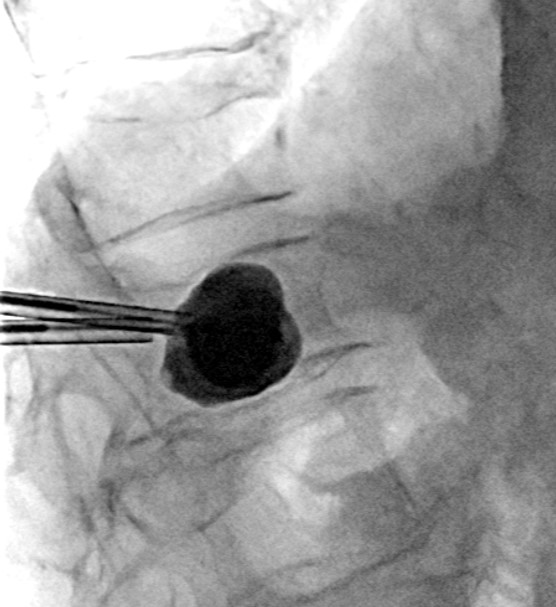

Doc. MUDr. Petr Vachata, Ph.D., MBA, vedoucí lékař Spondylochirurgického centra, provedl následně u druhého pacienta výkon formou kyfoplastiky. Během ní se kromě implantace kostního cementu pomocí zavedených tlakových balónů restauruje výška obratlového těla a fyziologická osa páteře. „V případě augmentačních výkonů je nejobávanější komplikací chybná pozice zavedených augmentačních kanyl, kdy může dojít k postižení nervových struktur s trvalými následky pro pacienta. Již před lety jsme v rámci neurochirurgie, s cílem zvýšit bezpečnost těchto výkonů, prohloubili spolupráci s radiodiagnostickou klinikou a začali provádět tyto augmentační výkony na rotační angiografii,“ vysvětluje docent Vachata.

Restaurace výšky zlomeného obratle kyfoplastickými balóny. Foto: Krajská zdravotní